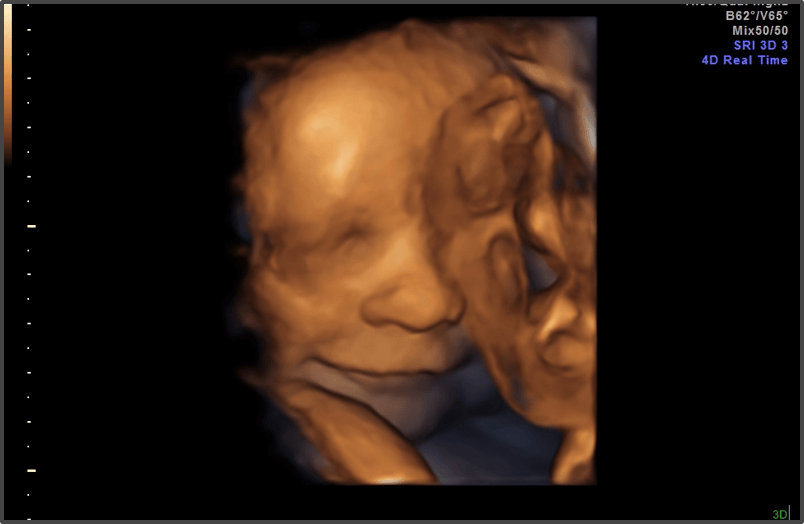

Your baby is the size of a pineapple.

Approx Baby Weight: 1.9kg

Approx Baby Size: 43.7 cm

Baby Development

The baby’s brain and nervous system are continuing to develop.